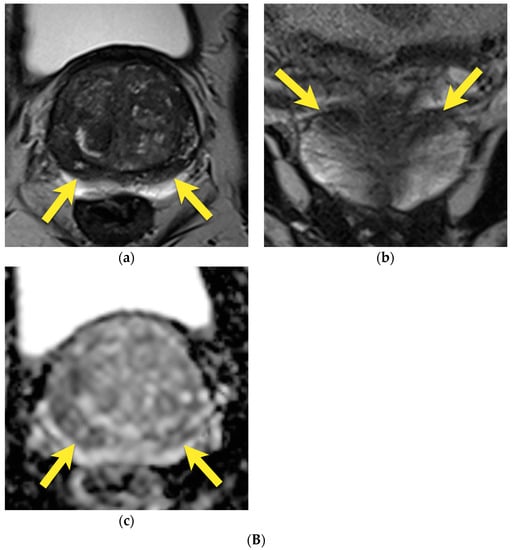

9. Prostatitis